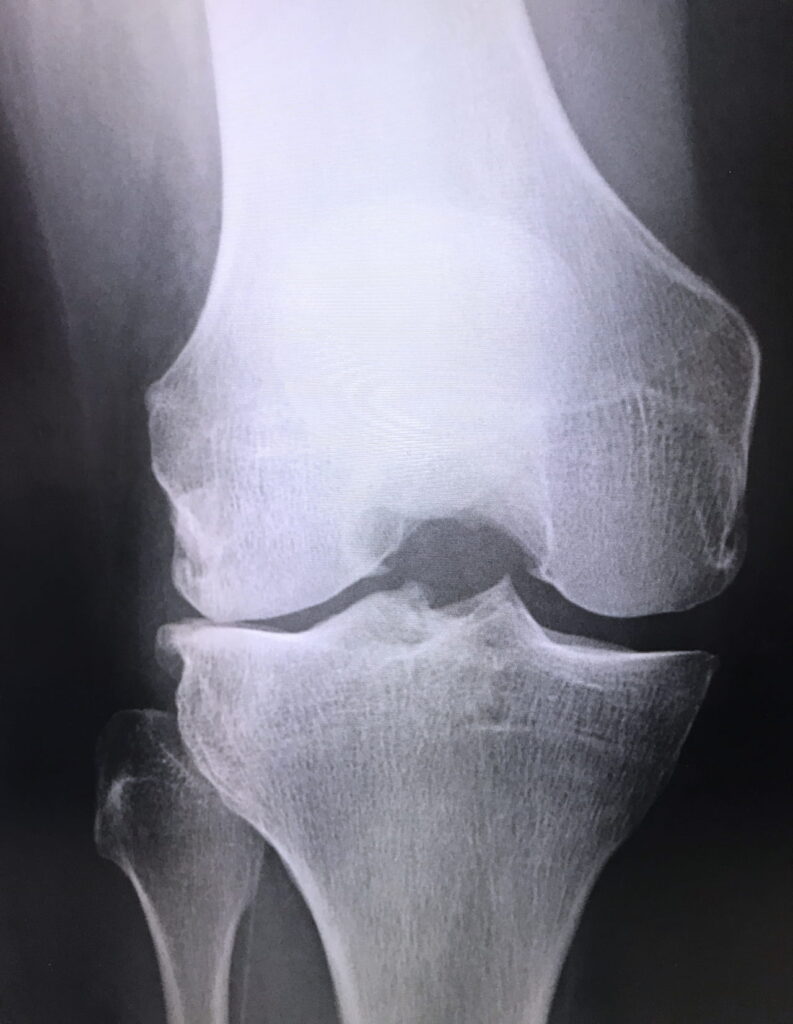

スポーツでの接触や交通事故など外からの強い衝撃により、軟骨の一部が欠けてしまうものです。軟骨が欠けるだけでなく、靱帯や半月板などが傷ついている場合もあります。

体重がかからないところの軟骨が欠け症状が軽い場合は、手術はせずに安静にしたり、痛み止めの薬などを使って治療します。体重がかかるところの軟骨が欠けた場合、4cm2未満であれば、その大きさによって骨穿孔術もしくは自家骨軟骨柱移植術とよばれる手術をおこないますが、4cm2以上の場合は「自家培養軟骨移植術」が可能です。

激しいスポーツなどで、ひざにくり返し力が加わることで、軟骨が軟骨の下にある骨とともに剥がれてしまうものです。

症状が軽いときは、安静にしているか骨穿孔術をおこないます。軟骨がすべて剥がれるなど症状が重い場合は、はがれた軟骨をピンで固定するか、骨穿孔術もしくは自家骨軟骨柱移植術とよばれる手術をおこないます。

はがれた軟骨の大きさが4cm2以上の場合は「自家培養軟骨移植術」が可能です。

10~20代の若者に多く、運動中に体重がかかった状態でひざをひねると損傷を受けやすくなります。階段昇降やしゃがみこみ動作などの運動時に痛みを感じ、ひざがひっかかるような感覚を覚えたり、屈曲したまま動かなくなるなどの症状がみられます。

半月板を縫い合わせたり、部分的に切り取るなどの治療を施します。